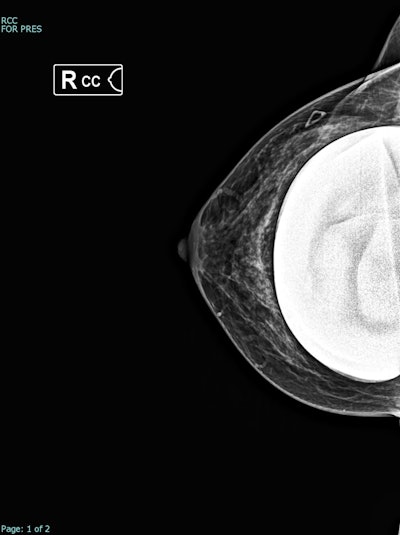

Synthesized 2D mammogram, right breast, craniocaudal (CC) projection of the same patient. No mammographic abnormality is seen. Sensitivity is markedly reduced by dense breast tissue. A retroglandular silicone breast implant is present.